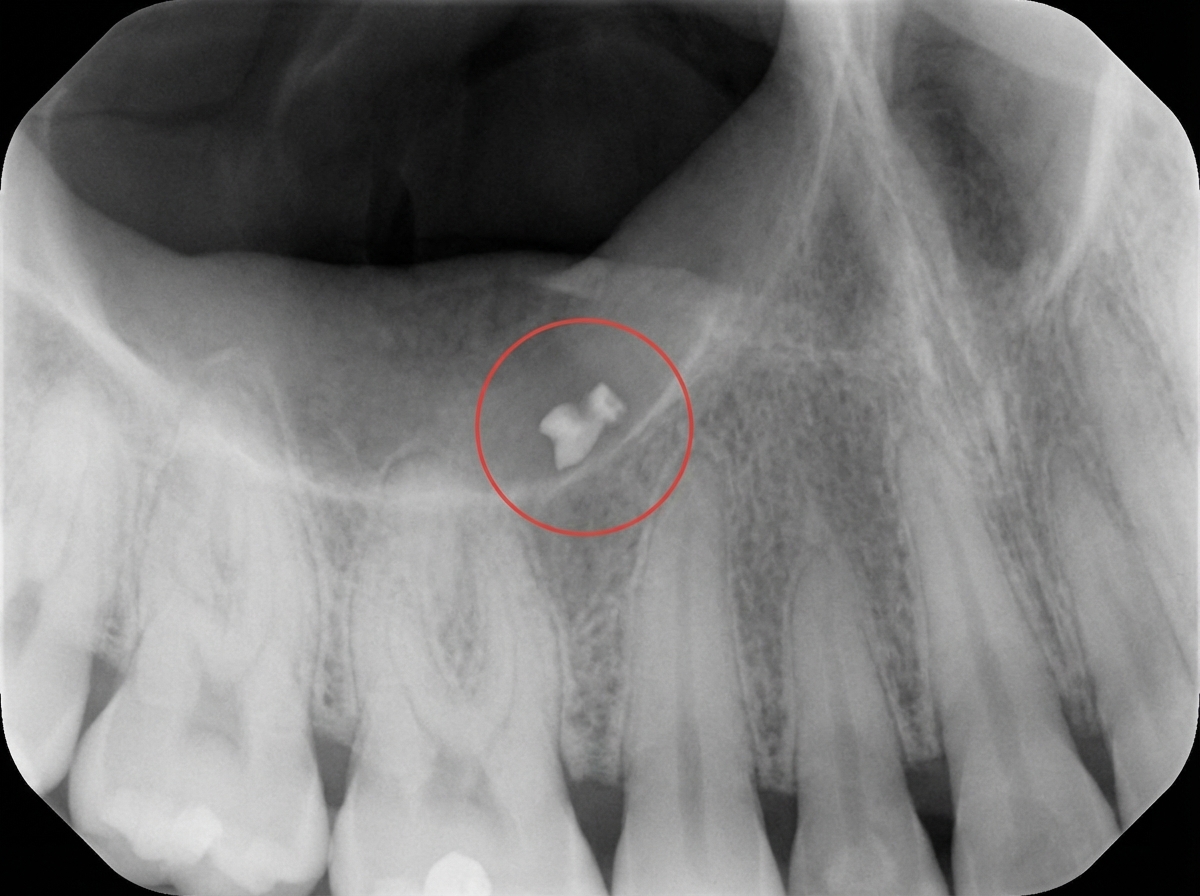

A 19-year-old boy presents with a swollen lip and fractured maxillary central incisors following trauma. The encircled area in the radiograph shows:

Explanation: ***Fragment of the fractured tooth*** - Following **dental trauma** with fractured central incisors, **tooth fragments** can become embedded in the soft tissues, particularly the lip, and appear as **radiopaque** structures on radiographs. - **Soft tissue radiographs** are essential in dental trauma cases to locate embedded **tooth fragments** that require surgical removal to prevent infection and foreign body reaction. *Calculus in the salivary duct* - **Sialolithiasis** (salivary stones) typically occurs in **major salivary ducts** like Wharton's duct or Stensen's duct, not in lip tissue. - These stones are usually associated with **salivary gland swelling** and **pain during eating**, which are not consistent with this trauma case. *Irritational calcinosis of the lips* - **Irritational calcinosis** is a rare condition involving **calcium deposits** in soft tissues due to chronic irritation, not acute trauma. - This condition typically develops over **months to years** and would not appear immediately following dental trauma. *None of the above* - Given the **clinical history** of dental trauma with fractured incisors and swollen lip, the radiopaque structure is most likely a **tooth fragment**. - The **temporal relationship** between trauma and radiographic findings makes tooth fragment the most probable diagnosis.